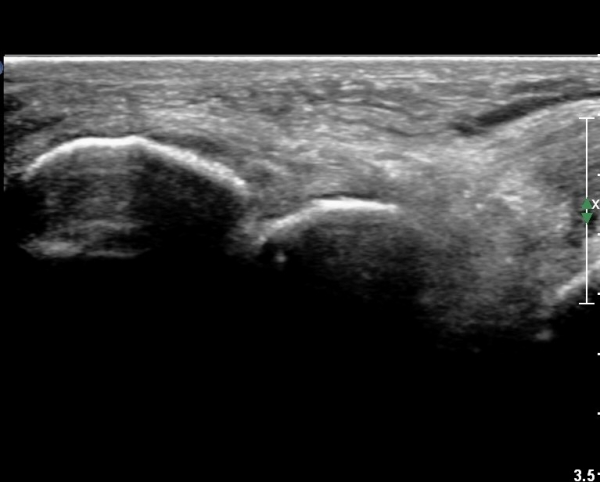

¹ß¸ñ ¾ÕÂÊ Á¾´Ü¸é°Ë»ç¿¡¼­ ¹ß¸ñ°üÀý³» °æ¹ÌÇÑ ¼ö¾×Àú·ù¸¦ º¸À̰í(»çÁø 1, 2)